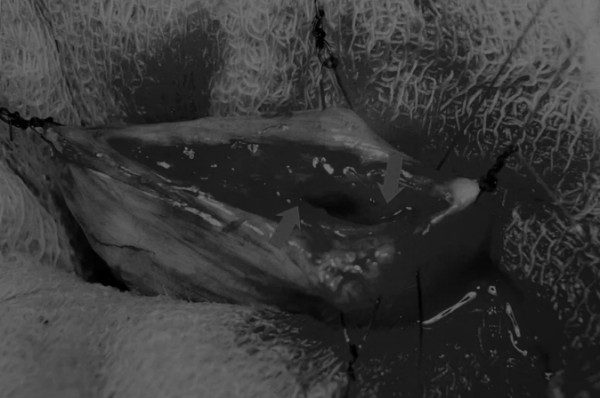

在牵引缝线之间选择血管扩张较差的区域用手术刀切开膀胱壁(图3)。在牵引缝合线之间用手术刀在血管不良的区域做切口。切开膀胱壁后,膀胱内的手术可按手术方案实施,例如取出结石(图4)。

图4 这张图显示了从膀胱中取出的大量结石

完成膀胱内冲洗后,应通过导尿管反向冲洗膀胱;砂样结石和血块会被冲到切口表面(图5)

图5 通过导尿管注入无菌生理盐水反向冲洗,可以去除微小的结石(箭头)和夹杂在膀胱黏膜皱褶中的砂样结石,以及可能在手术中形成的血块